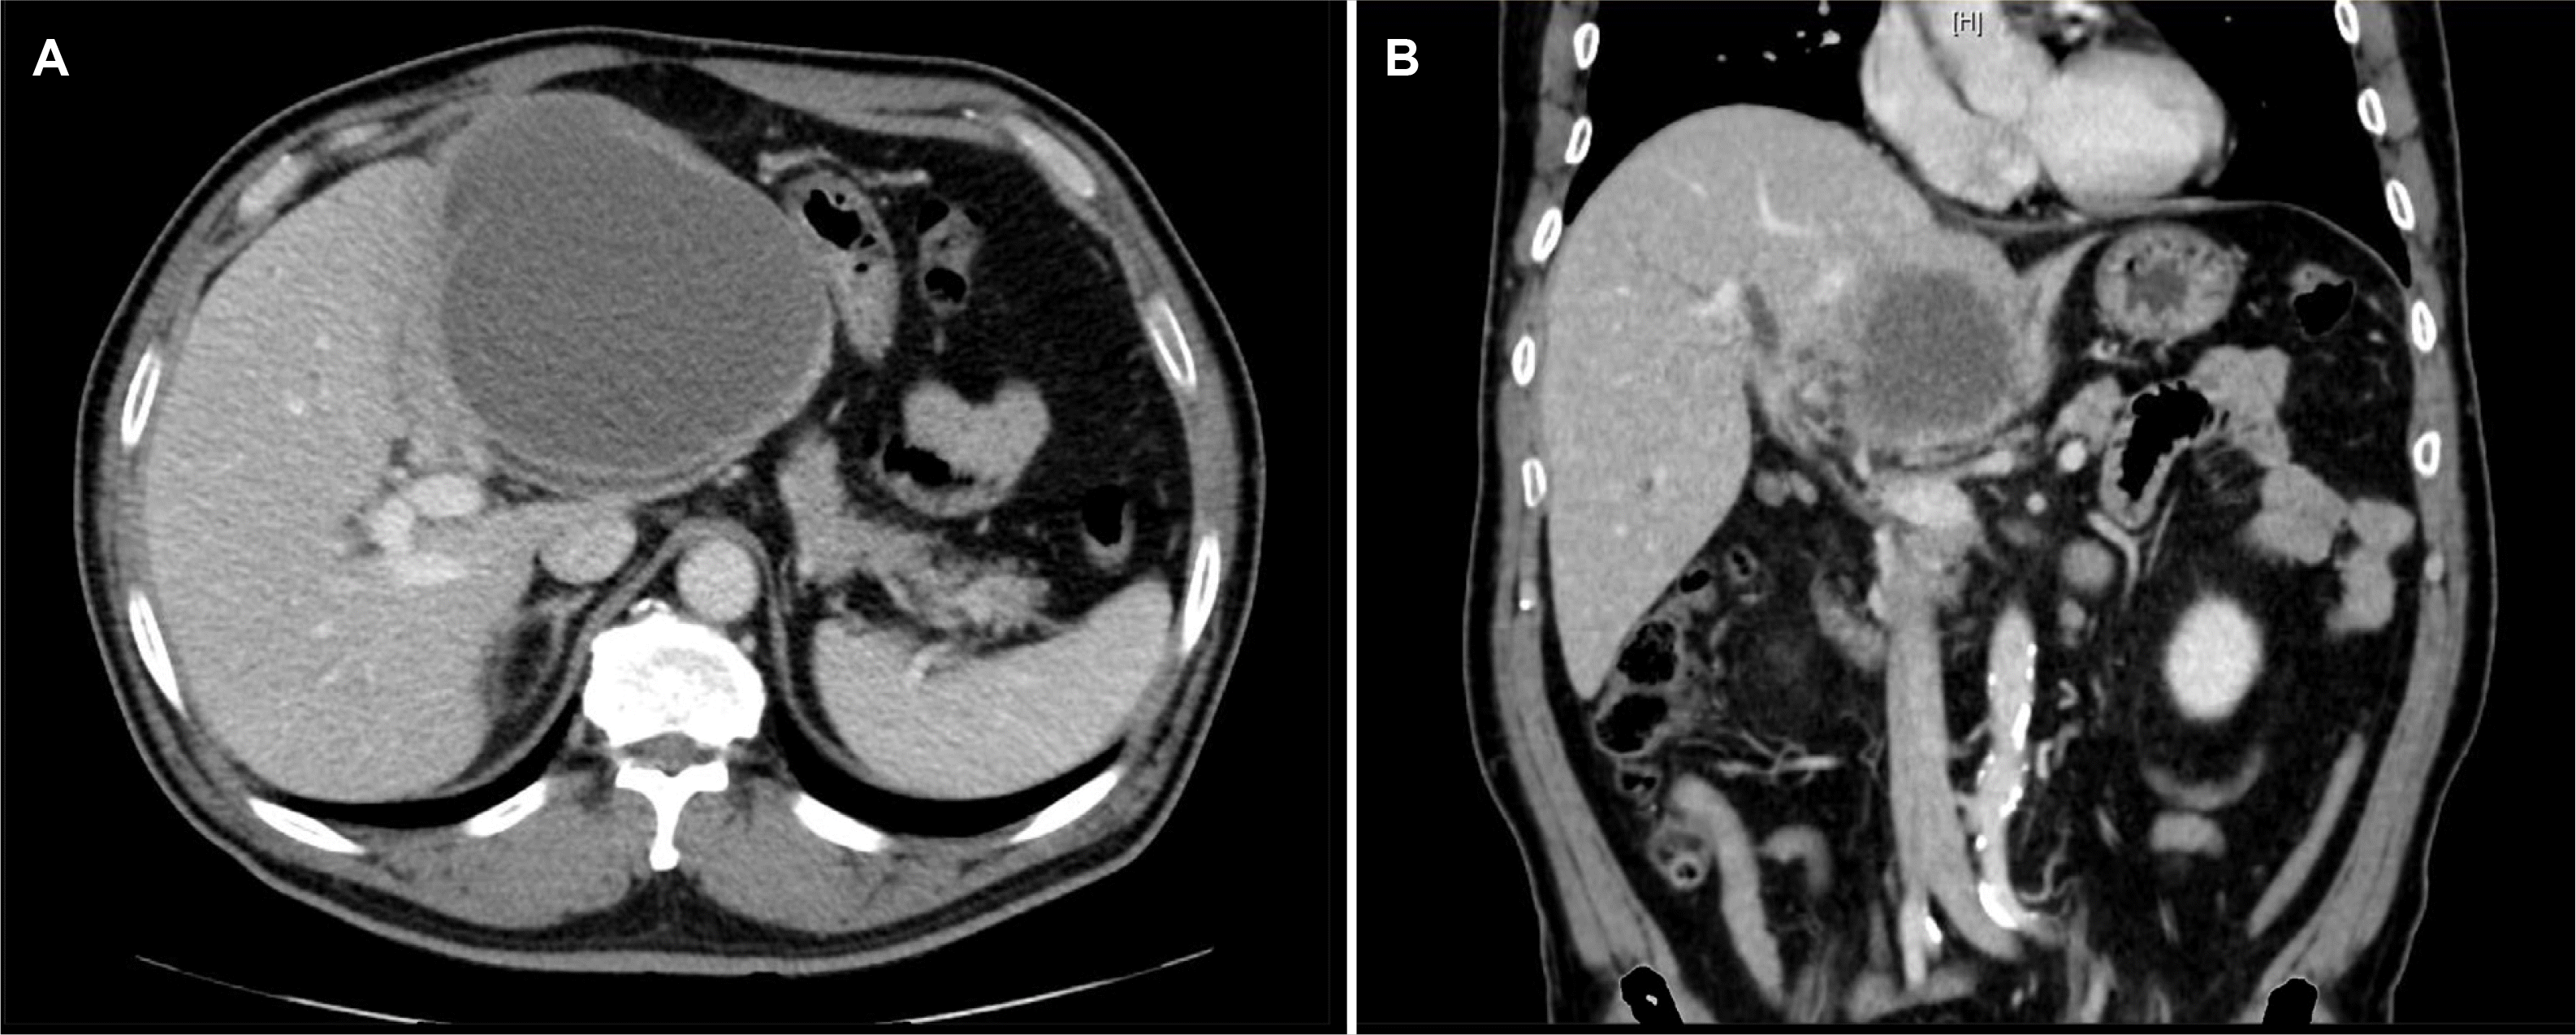

Fig. 7

Contrast-enhanced biliary CT image taken 22 days after inserting the PTBD (A) The cystic component still has a PCD inserted and appears more collapsed than before. (B) The cholangiocarcinoma in the left liver shows no significant change in the size of the solid portion; it continues to invade around the hilar duct. CT, computed tomography; PTBD, percutaneous transhepatic biliary drainage; PCD, percutaneous catheter drainage.

Initially, empirical antibiotic treatment with moxifloxacin was started, and percutaneous catheter drainage (PCD) was performed to manage the suspected liver abscess. The drainage fluid was yellowish and turbid, with the analysis showing a white blood cell count exceeding 100,000 cells/mm³ with 97% polymorphonuclear neutrophils, a protein level of 1,490 mg/dL, an albumin concentration of 940 mg/dL, and a CEA level of 10,600 ng/mL. The cytology of the fluid revealed a few atypical cells, but subsequent evaluations were negative for malignant cells (Fig. 4). The entamoeba histolytica IgG serology was negative. No growth was observed in cultures. A liver biopsy performed six days after sufficient drainage revealed a moderately differentiated adenocarcinoma with tumor necrosis, leading to the final diagnosis of primary cholangiocarcinoma (Fig. 5). Positron emission tomography-computed tomography revealed hypermetabolic lesions in segment 4 and the right internal mammary nodal chain (Fig. 6). A biliary CT was performed 22 days after inserting the PCD, which showed that the abscess had collapsed compared to previous imaging. On the other hand, the lesion suspected to be cholangiocarcinoma showed no significant change (Fig. 7). The PCD output remained consistently brown-yellowish, with daily volumes ranging from 100 to 150 cc since its insertion, and never decreased below 50 cc. The drainage characteristics were not thick or pus-like, and the output remained stable despite being drained for more than 21 days, which reduced the likelihood of a liver abscess. Consequently, the catheter was maintained in situ. Nevertheless, the drainage volume remained above a certain level, so the patient continued the drainage while initiating systemic chemotherapy.